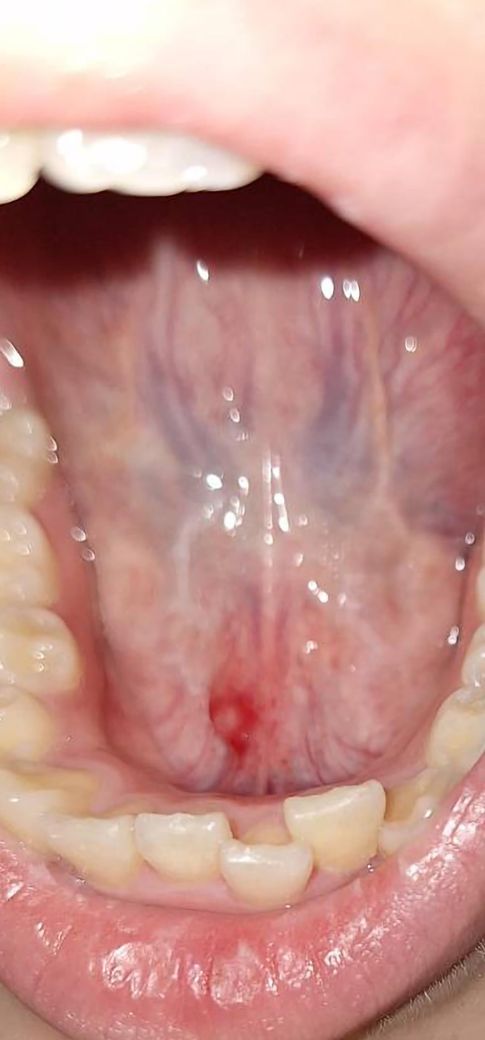

갑자기 혀 아래가 아파서 봤더니 이렇게 돼있더라구요.. 괜찮을까요....?

갑자기 혀아래 통증이 있어 혀 아래를 봤더니 이렇게 빨간색으로 올라와 있더라구요.. 여기서 피도 조금씩 나오고 괜찮을까요..?

• 1번 째 사진